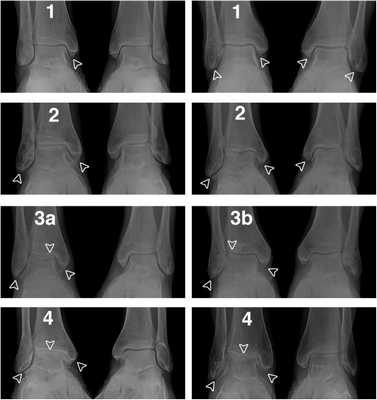

Классификация переломов лодыжек по Weber and Danis

Чем выше перелом малоберцовой кости, тем обширнее повреждение межберцовых связок и потому больше опасность возникновения недостаточности функции вилки голеностопного сустава. Существуют три типа повреждения в зависимости от уровня перелома малоберцовой кости (рис. 14.4).

Тип А (44-А1-3)

Малоберцовая кость: Поперечный отрывной перелом на уровне или ниже уровня голеностопного сустава (рис. 14.4а) или разрыв латерального связочного аппарата (рис. 14.4а').

Тип В (44-В1-3)

Малоберцовая кость: Косой или торзионный перелом, начинающийся от уровня голеностопного сустава и идущий в проксимальном направлении (рис. 14.4b). Линия перелома может быть гладкой или изломанной, что зависит от приложенной силы.

Тип С (44-С1-3)

Малоберцовая кость: Перелом диафиза в любом месте между синдесмозом и головкой малоберцовой кости (рис. 14.4с,d).

Тяжесть повреждения связочного аппарата и тяжесть перелома лодыжек возрастают прогрессивно от перелома типа А к типу В и типу С.

Оценка рентгенограмм.

А Вид сустава на рентгенограмме при ротации стопы кнутри на 20": просвет сустава имеет везде одинаковую ширину. Субхондральные костные пластинки таранной и большеберцовой костей расположены параллельно. Линия субхондральной пластинки большеберцовой кости, проецируемая через щель, является продолжением субхонд-ральной линии латеральной лодыжки без образования ступени.

А' Любое, даже минимальное, укорочение наружной лодыжки ведет к образованию ступени между субхондраль-ными линиями большеберцовой и малоберцовой кости на рентгенограмме в прямой проекции. Латеральное смещение таранной кости приводит к соответствующему расширению просвета сустава с внутренней стороны.

B Стрессовая рентгенограмма голеностопного сустава в прямой проекции. Обратите внимание на наклон таранной кости на 10º. Это указывает на повреждение Lig. calcaneofibulare и в большинстве случаев также и на разрыв lig. fibulotalare anterius.

С Боковая стрессовая рентгенограмма без признаков подвывиха таранной кости.

С' Передний подвывих таранной кости. Разница между шириной просвета сустава с поврежденной и неповрежденной стороны в 3,0 мм и более является патогномоничным признаком повреждения Lig. fibulotalare anterius.